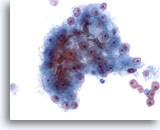

画像 4

肝FNA – 良性肝細胞

反応性変化を来した肝細胞。核は大小不同で、二核を有しています。

40倍

画像 4

肝FNA – 良性肝細胞

反応性変化を来した肝細胞。核は大小不同で、二核を有しています。

40倍